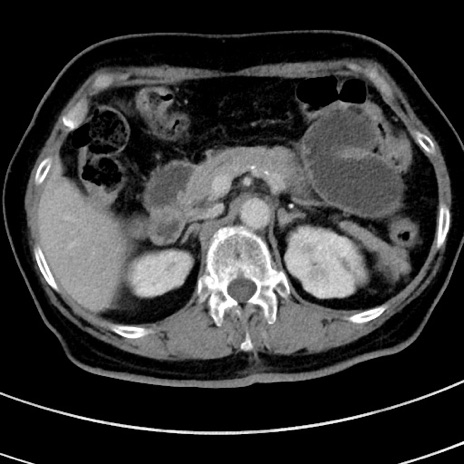

症例9(横断像)

【症例】 60歳代女性

【主訴】むかつき、みぞおちの痛み

【現病歴】3日前よりむかつきがあり、食事がとれない。

【既往歴】糖尿病

【身体所見】発熱なし、心窩部圧痛軽度あるも、腹膜刺激症状なし。

【データ】WBC 7400、CRP 1.92